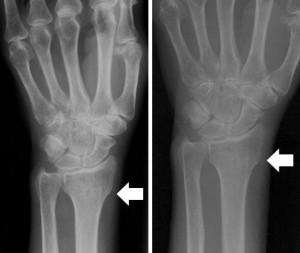

Диагностическое заключение производится на основе анамнеза, врачебного осмотра и рентгена. Если спровоцировать сильное вытяжение сустава как можно быстрее после травмы, то такой вывих довольно легко вправляется. Для этого специалисту требуется взять пострадавшего за большой палец, а остальные пальцы резко оттянуть в противоположную сторону. Данная манипуляция позволяет правильно сопоставить отломок шиловидного отростка и лучевую кость.

В случае если медицинские процедуры обеспечили абсолютную репозицию отломков костей, больной полноценно восстанавливает объем движений. Перед снятием гипса доктор делает контрольную рентгенографию, чтобы убедиться в срастании перелома.